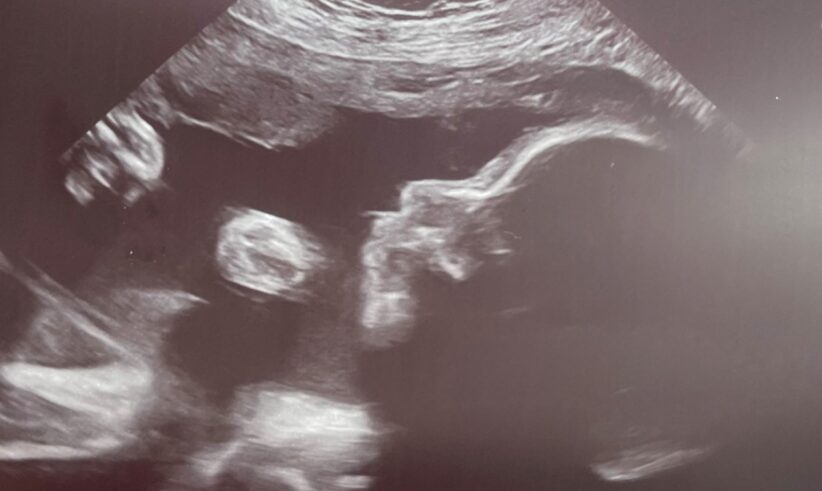

But when Cady happened to glance in the trash to throw something away, she saw the two lines. In disbelief, she grabbed it out and rushed to show Alex who told her right away to take another one. Sure enough, it was positive too. They graduated from CCRM at 8.5 weeks and are due in July.